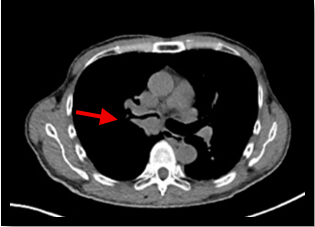

肺がん原発巣の症例。(病変部は赤矢印)

CT画像→病変部がわかりにくい

PET画像とCT画像を重ね合わせることで、病変が存在する解剖部位が分かるため診断能が高くなる